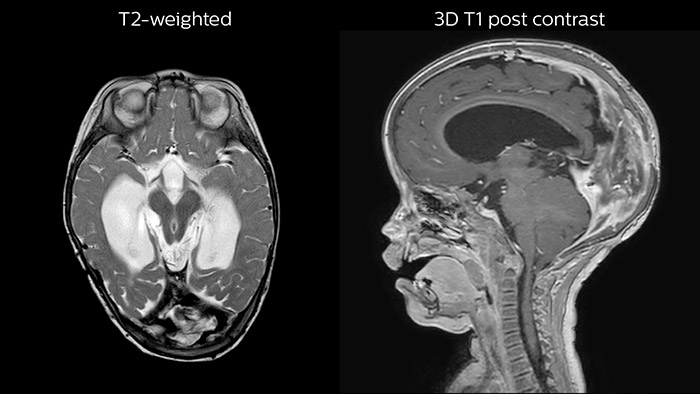

Hydrocephalus post hemorrhagic

Both pictures show a ventriculoperitoneal shunt. With our previous scanner our hydrocephalus protocol needed about 25 min. With Ambition the examination time is about 14 min. including a CSF PCA sequence to show flow in the aqueduct.